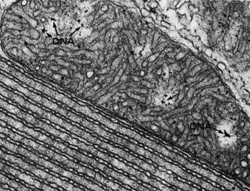

Mitochondria are structures within cells often referred to as “power

houses” because they generate most of cells’ energy. Unlike other cell

structures, they contain their own DNA — separate from that enclosed in

the nucleus — in the form of two to 10 small, circular chromosomes that

code for 37 genes necessary for mitochondrial function. There are 10 to

thousands of mitochondria per cell, depending on a cell’s energy needs.